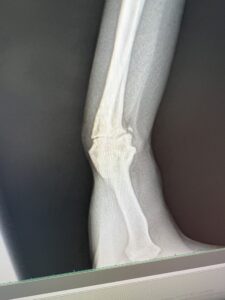

まげたりのばしたり、色々診てもらってレントゲン。

そしたらさ・・・・

折れたりヒビははいっていないんだけども・・・・

これーーーーーー!!!!

なぜかここにあるこれ。

骨が欠けたみたいです。(´;ω;`)ウゥゥ

これは痛いわ!

だってないものがここにあるんだもの・・・・